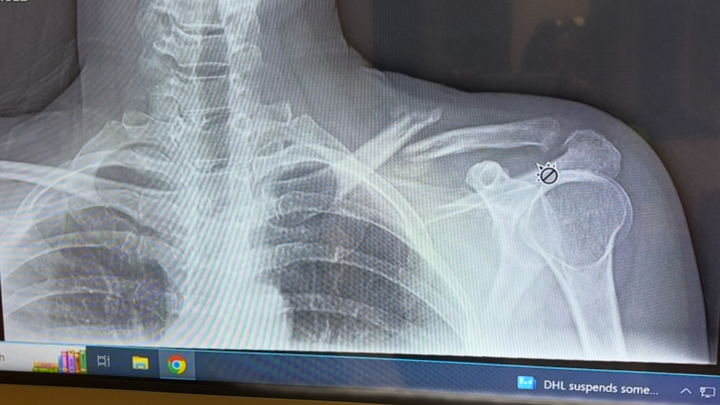

Hey friends and family, my name is April. I had a bad fall and broke my collarbone and kneecap. To try to avoid surgery, I'll be starting PT ASAP. I just started working again prior to the injury. I am asking for a little help to take some pressure off my sweetheart who has to carry me once again financially. Bills are piling up like crazy. Thank you kindly ❤️ I’ll be posting the pictures of the X-rays of my knee and shoulder very soon. My deductible is crushing us so I’ve opted to do PT at home for my knee. I’ll only have to go in for my shoulder. Thank you for your help, love and support!

thank you so much for your donations! I was able to get caught up with my health insurance and put some money towards the cc that I have maxed out using it for my doctor visits. I greatly appreciate your help. Please share my fundraiser with your friends and family. Any little amount helps greatly. I am so bummed to be out of work again. Staying positive and plugging along. Doctor said 6 weeks for my kneecap to heal. Shoulder Dr wants to see how I’m healing before we have to do surgery which would entail re breaking it, bone grafting along with a plate. After that heals , he would go back in to remove the plate. Praying I don’t have to go that route.

I saw the shoulder doctor today. Shoulder is slowly healing but I’m devastated as he said it will alway be messed up and slump down and forward. Also because of this and my knee , I feel again and have done something really back to my back. Having multiple severe spasms. I am going to see a spine specialist asap. Being in the car is super painful. Walking , but mostly sitting . Bummed. Thank you all for your support and kindness.